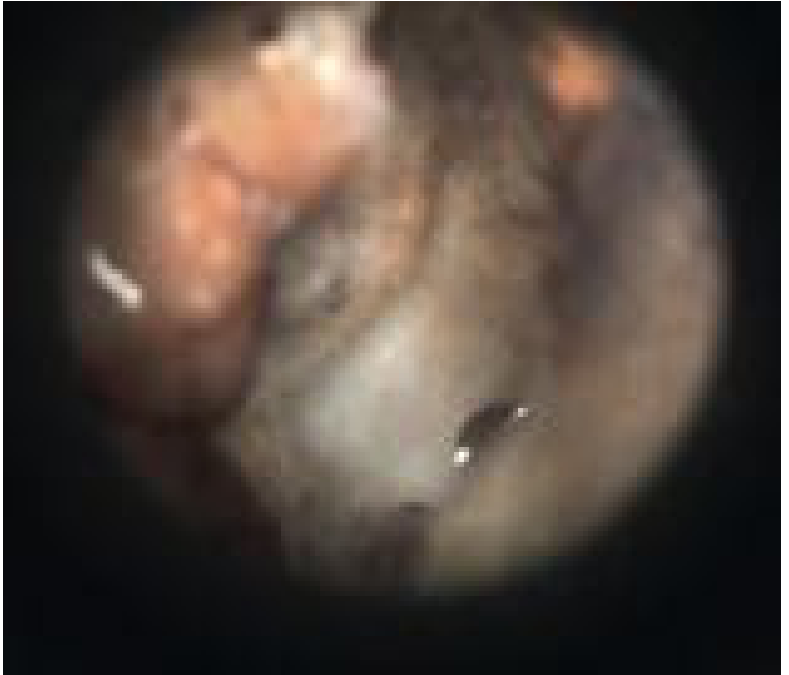

Malignant otitis externa — granulation tissue on the floor of the EAC

MOE: Granulation tissue at the bony-cartilaginous junction — Cummings Otolaryngology, Fig. 138.3